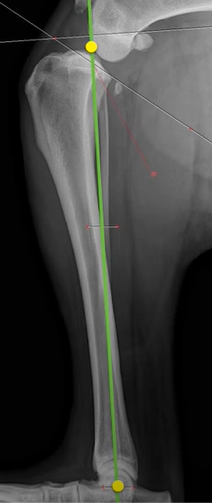

The dataset used for training was collected from various veterinary clinics, as none is available in the public domain, and the objects of interests were manually annotated. The resolution of these images vary largely as they are collected from various sources, thus for the sake of uniformity the images are all scaled to fit the same dimensions. The first part of this project was to develop a lightweight radiograph image sorting algorithm reported in [8]. The images chosen for the task described in this manuscript were all classified to be lateral lower body images by that sorting algorithm. Examples of manual annotations of objects of interests are given in Fig. 4: here regions A, B and C identify the joints while the point ’e’ identifies the centre of Talus and regions d1 and d2 identify the points that form the MTPL.

Most of the source dataset of over a thousand unique knee radiographs were distorted, had poor patient positioning, or were otherwise unfit for annotating. 250 of the original images were of sufficient quality to contribute to this effort. These images were set to have 6 different classes for training purposes, as mentioned and shown in Fig. 4. These were then trained using YOLOv3 [10] and the results of the predicted annotations are shown in Table I. From these predictions the centroids were extracted, which is then used to plot the FTL and MTPL. Then using the method mentioned in Section II, TPA is calculated. Examples of images, the region of interests detection and their respective TPA determination is shown in Fig. 6 and Table I: